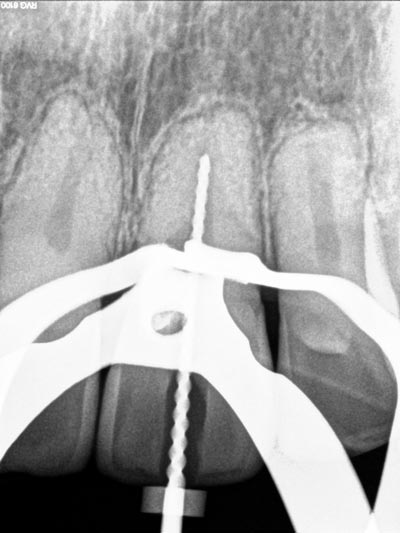

Imágenes: Endodoncia en un molar inferior izquierdo